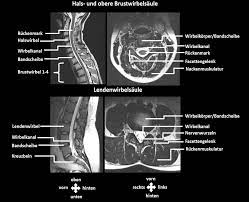

Mrt Bild Lendenwirbelsaule Bandscheibe Hat Jemand Ahnung Gesundheit Und Medizin Ruckenschmerzen Bandscheibenvorfall Lws